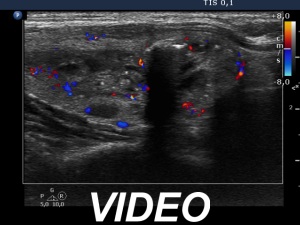

Ultrasonography. The thyroid was echonormal. There were two nodules in the right lobe, a dominantly cystic one, and a lesion in the lower third which had macrocalcifications. There was a minimally hypoechoic lesion in the left lobe which showed halo sign and perinodular vascularity. Compared with the first examination, the nodule in the left lobe showed a substantial increase, this time the dimensions were 15x14x17 mm.

The ultrasound presentation of the left lobe is almost diagnostic of follicular tumor, a solitary, homogeneous lesion presenting halo and perinodular blood flow has more than 90% risk being a follicular tumor.